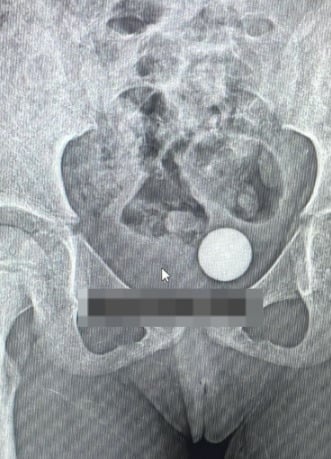

经过X光检查后发现,该女童阴道的深处有一个异物。

他在照片上的配文写道:“该异物是一颗玻璃弹珠,导致女童的处女膜撕裂。我们立即进行了手术取出玻璃弹珠,然后进行了处女膜修复手术。”